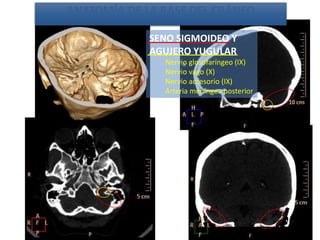

SENO SIGMOIDEO Y

AGUJERO YUGULAR

Nervio glosofaríngeo (IX)

Nervio vago (X)

Nervio accesorio (IX)

Arteria meníngea posterior